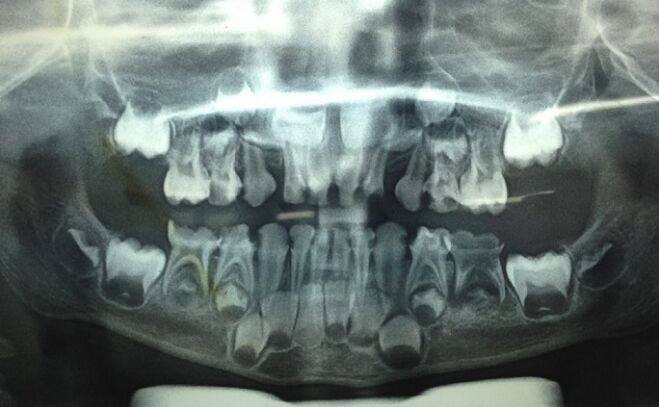

35.5歲男童右下牙齦反覆出現膿腫(abscess),所拍攝的放射線影像如圖示;關於治療方式,下列敘述何者錯誤? (A)第一乳臼齒可施行樹脂填補 (B)膿腫發生的主因是第二乳臼齒鄰接面齲齒 (C)第二乳臼齒可施行牙髓切除術(pulpectomy)或拔除乳牙 (D)考量到拔除第二乳臼齒可能造成空間喪失,牙髓切除術(pulpectomy)可能是較好的選擇

44.5歲孩童下顎左側乳臼齒深度齲齒需拔除(如下圖)建議使用何種空間維持器?(A)帶環裝置(band and loop space maintainer) (B)遠心鞋型裝置固定型(distal shoe space maintainer-fixed type) (C)舌側牙弓維持器(lingual holding arch) (D)冠環裝置(crown and loop space maintainer)